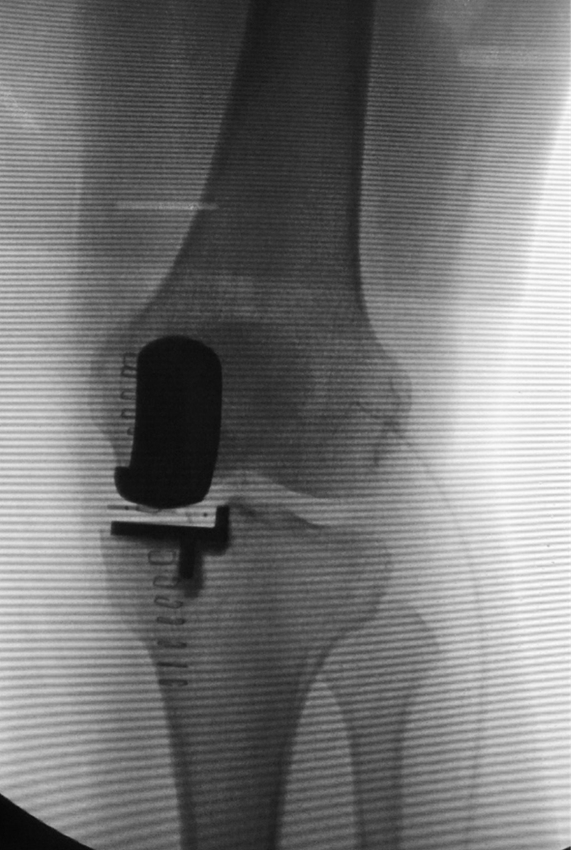

术中膝关节侧位X线